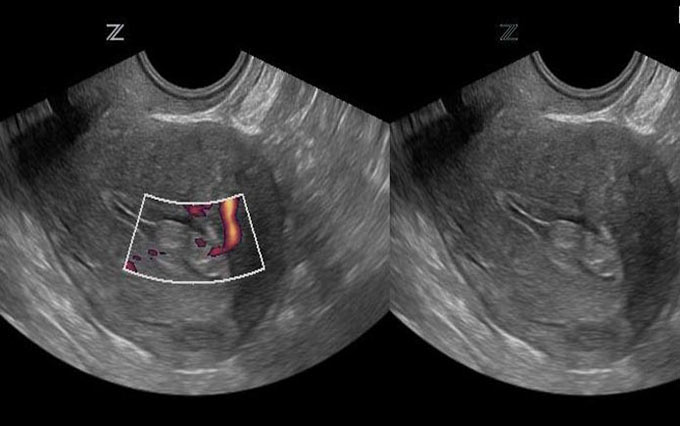

Полип может обнаружить врач при осмотре. Как правило, для этого используется кольпоскоп — специальный прибор, позволяющий провести более тщательный осмотр влагалища и части шейки матки. Также используется ультразвуковая диагностика, но ее следует использовать в определенные дни цикла — на третий или пятый день — чтобы отличить слой эндометрия от полипа матки.

В большинстве случаев патологический процесс протекает бессимптомно: полип, растущий в цервикальном канале, никак себя не проявляет. Эта патология обычно обнаруживается при осмотре гинекологом или при кольпоскопии при плановом осмотре или при обращении к другой проблеме. Иногда можно заподозрить наличие полиповидного образования при УЗИ органов малого таза.

Инструментальные методы обследования

В отличие от полипов эндометрия, которые в большинстве случаев легко диагностируются с помощью трансвагинального УЗИ, выявление полипов цервикального канала представляет определенные трудности [1]. Это связано с особенностями расположения образований и их строением. Например, железистый полип очень похож по строению на миометрий шейки матки, что затрудняет диагностику, особенно если он имеет небольшие размеры [3] [5]. Этот метод исследования используется для дифференциальной диагностики с полипами эндометрия, расположенными в полости матки, и помогает максимально точно установить локализацию данной патологии.